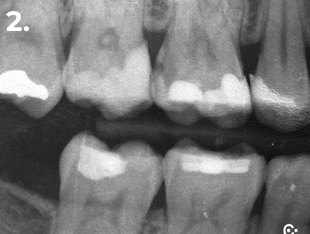

Esame clinico e radiografico:

• Restauro composito occluso-mesiale

• Carie distale profonda

Diagnosi: Pulpite reversibile

Il paziente si presenta alla visita riferendo fastidio nella zona del primo quadrante. L’esame clinico e radiografico evidenzia la presenza di una carie distale profonda, portando alla diagnosi di pulpite reversibile. Al fine di ottenere un adeguato punto di contatto sia mesiale che distale, si è proceduto alla rimozione completa del restauro preesistente.

Fig. 2 Radiografia bitewing iniziale